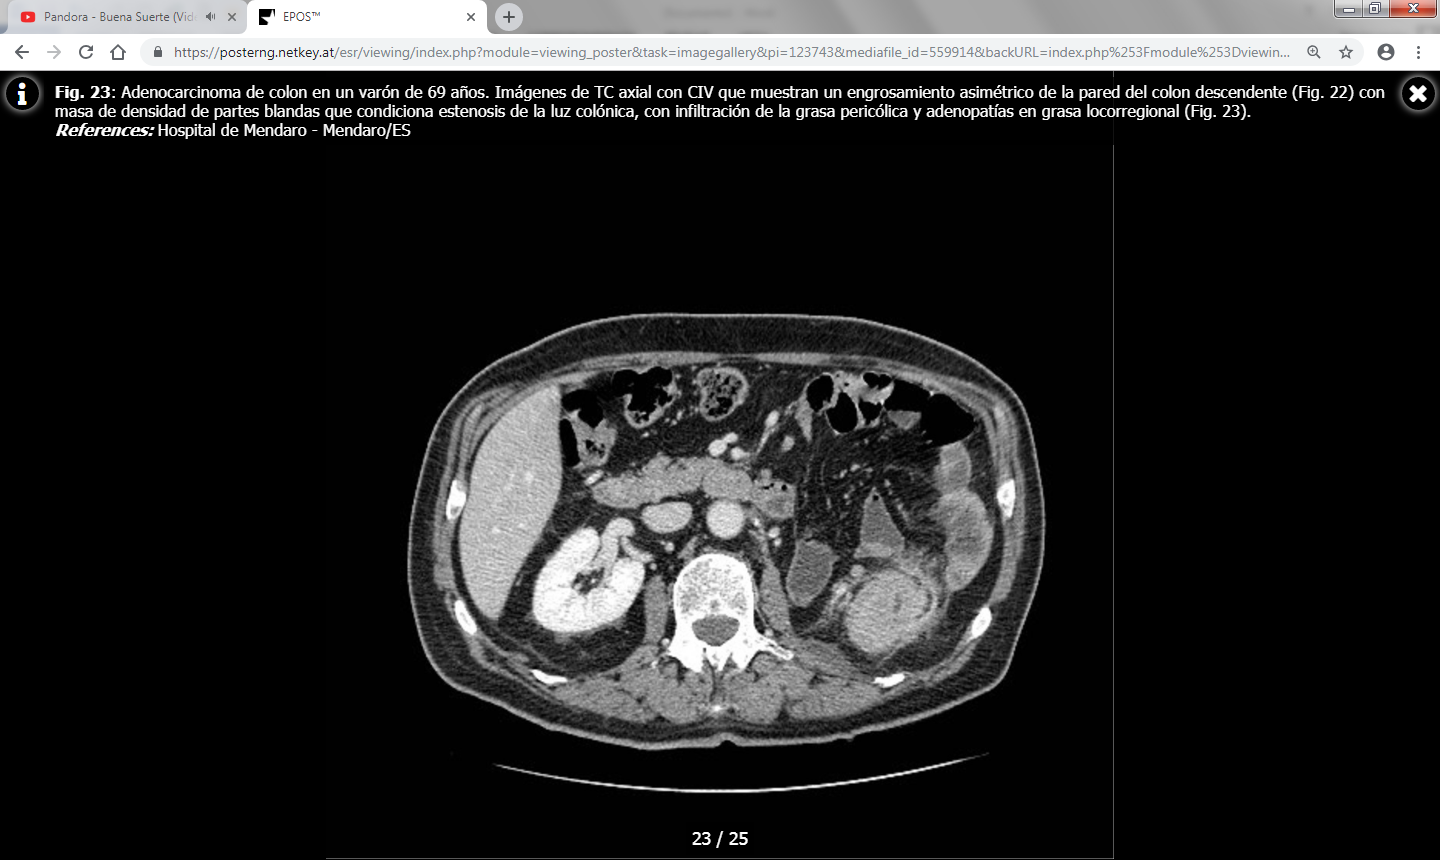

La TC juega un papel importante en el estudio de extensión del carcinoma colorrectal y en la detección de recurrencias.

Los hallazgos en TC incluyen una masa de densidad de partes blandas de contornos irregulares o un engrosamiento parietal focal asimétrico que condicionan estenosis de la luz colónica. Las masas de mayor tamaño pueden presentar un centro necrótico de baja atenuación y ocasionalmente pueden contener gas.